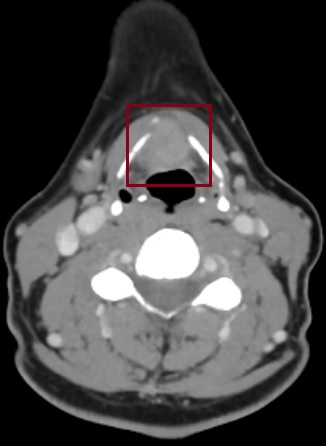

Ασθενής 51 ετών πρσήλθε με δυσφωνία με επίταση της συμπτωματολογίας σε διάστημα δύο μηνών. Η βιοψία της βλάβης στα πλαίσια πανενδοσκόσης κατέδειξε την ύπαρξη πλακώδους καρκινώματος στο πρόσθιο τριτημόριο αμφότερων των γνησίων και των νόθων φωνητικών χορδών. Η αξονική τομογραφία κατέδειξε την ύπαρξη μίας χωροκατακτητικής εξεργασίας με προσβολή της πρόσθιας εντομής και εκτεταμένη διάσπαση του θυρεοειδικού χόνδρου (Εικόνα). Μετά από λεπτομερή παρουσίαση του περιστατικού στο ογκολογικό συμβούλιο συστήθηκε στον ασθενή και πραγματοποιήθηκε με επιτυχία αφαίρεση του όγκου υπό τη μορφή λαρυγγεκτομής με τοποθέτηση φωνητικής πρόθεσης και αμφοτερόπλευρος λεμφαδενικός καθαρισμός. Ο ασθενής έλαβε εξιτήριο την 7η μετεγχειρητική ημέρα σε άριστη κατάσταση.